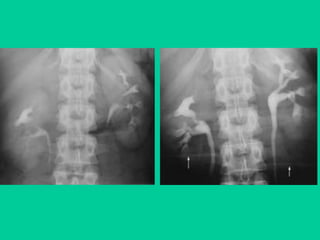

NHIEÃM KYÙ SINH TRUØNG

Coù theå laø caùc ñoùng voâi ôû thaønh

nang saùn vôùi daïng voøng hay daïng

quaû leâ.

Nang KST coù theå kheùp kín, nhöng ña

soá môû vaøo moät ñaøi thaän neân

thaáy

ñöôïc

bôø

ngoaøi

khi

chuïp

ñöôøng nieäu vôùi thuoác caûn quang.

Caùc

nang

lôùn

“daughter cyst”.

coù

theå

chöùa

NHIEÃM ECHINOCOCCUS NIEÄU

NHIEÃM SCHISTOSOMIA NIEÄU